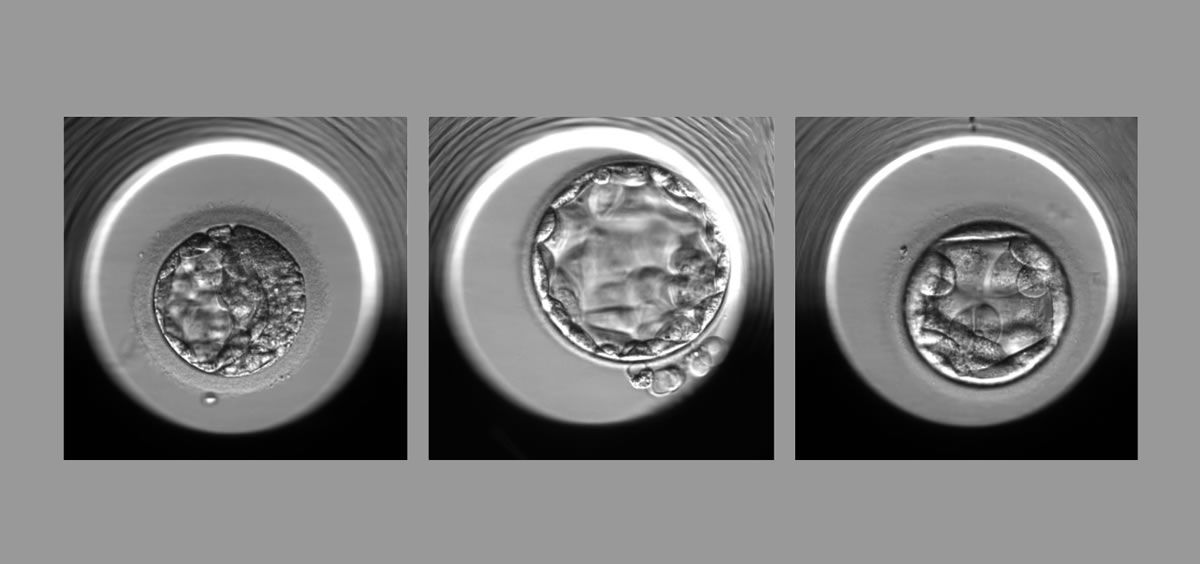

El nuevo algoritmo, STORK-A, descrito en un artículo publicado el 19 de diciembre de 2022 en Lancet Digital Health, puede ayudar a predecir la aneuploidía sin las desventajas de la biopsia. Funciona mediante el análisis de imágenes microscópicas del embrión e incorpora información sobre la edad materna y la puntuación de la clínica de FIV sobre la apariencia del embrión.

El personal de la clínica de fertilidad usa, en la actualidad, microscopía para evaluar embriones en busca de anomalías a gran escala que se correlacionan con una viabilidad deficiente. Para obtener información sobre los cromosomas, el personal clínico también puede usar un método de biopsia llamado prueba genética preimplantacional para aneuploidía (PGT-A), fundamentalmente en mujeres mayores de 37 años.

Para desarrollar un enfoque computacional para la evaluación de embriones que aprovechó el uso pionero de la fotografía de lapso de tiempo del Laboratorio de Embriología, para lo cuál los investigadores del Centro de Medicina Reproductiva se asociaron con sus compañeros del Instituto Englander.